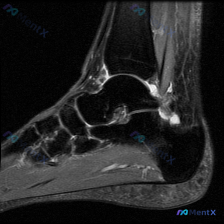

这是一张膝关节MRI(T2序列)轴位图像,层面覆盖膝关节前部,包含髌骨、股骨滑车及周围软组织结构:

- 髌骨:骨皮质信号缺失(低信号),髓腔信号正常,皮质连续性尚可,无明显骨折线

- 股骨滑车:位于髌骨后方,可见内外侧髁形成的滑车沟,无显著骨髓水肿

- 髌股关节间隙:可见明显异常高信号,提示存在关节积液

- 髌骨外侧旁及外侧支持带区域:可见弥漫性异常高信号,伴软组织肿胀,提示广泛软组织水肿

- 关节软骨:未见明显局限性软骨缺损或剥脱,本序列层面无法全面评估